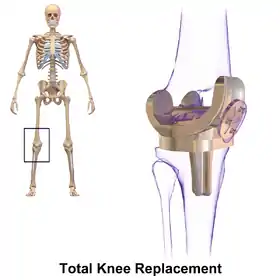

Knee replacement, also known as knee arthroplasty, is a surgical procedure to replace the weight-bearing surfaces of the knee joint to relieve pain and disability, most commonly offered when joint pain is not diminished by conservative sources[1][2] and also for other knee diseases such as rheumatoid arthritis and psoriatic arthritis. In patients with severe deformity from advanced rheumatoid arthritis, trauma, or long-standing osteoarthritis, the surgery may be more complicated and carry higher risk. Osteoporosis does not typically cause knee pain, deformity, or inflammation and is not a reason to perform knee replacement.

Knee replacement surgery can be performed as a partial or a total knee replacement.[3] In general, the surgery consists of replacing the diseased or damaged joint surfaces of the knee with metal and plastic components shaped to allow continued motion of the knee.

The surgery involves exposure of the front of the knee, with detachment of part of the quadriceps muscle (vastus medialis) from the patella. The patella is displaced to one side of the joint, allowing exposure of the distal end of the femur and the proximal end of the tibia. The ends of these bones are then accurately cut to shape using cutting guides oriented to the long axis of the bones. The cartilages and the anterior cruciate ligament are removed; the posterior cruciate ligament may also be removed but the tibial and fibular collateral ligaments are preserved.[16] Whether the posterior cruciate ligament is removed or preserved depends on the type of implant used, although there appears to be no clear difference in knee function or range of motion favouring either approach.[16] Metal components are then impacted onto the bone or fixed using polymethylmethacrylate (PMMA) cement. Alternative techniques exist that affix the implant without cement. These cement-less techniques may involve osseointegration, including porous metal prostheses. Finally, stability and range of motion is checked, followed by irrigation, hemostasis, placement of hemovacs, and closure.[17]

Femoral replacement

A round ended implant is used for the femur, mimicking the natural shape of the joint. On the tibia the component is flat, although it sometimes has a stem which goes down inside the bone for further stability. A flattened or slightly dished high-density polyethylene surface is then inserted onto the tibial component so that the weight is transferred metal to plastic not metal to metal. During the operation any deformities must be corrected, and the ligaments balanced so that the knee has a good range of movement and is stable and aligned. In some cases the articular surface of the patella is also removed and replaced by a polyethylene button cemented to the posterior surface of the patella. In other cases, the patella is replaced unaltered.